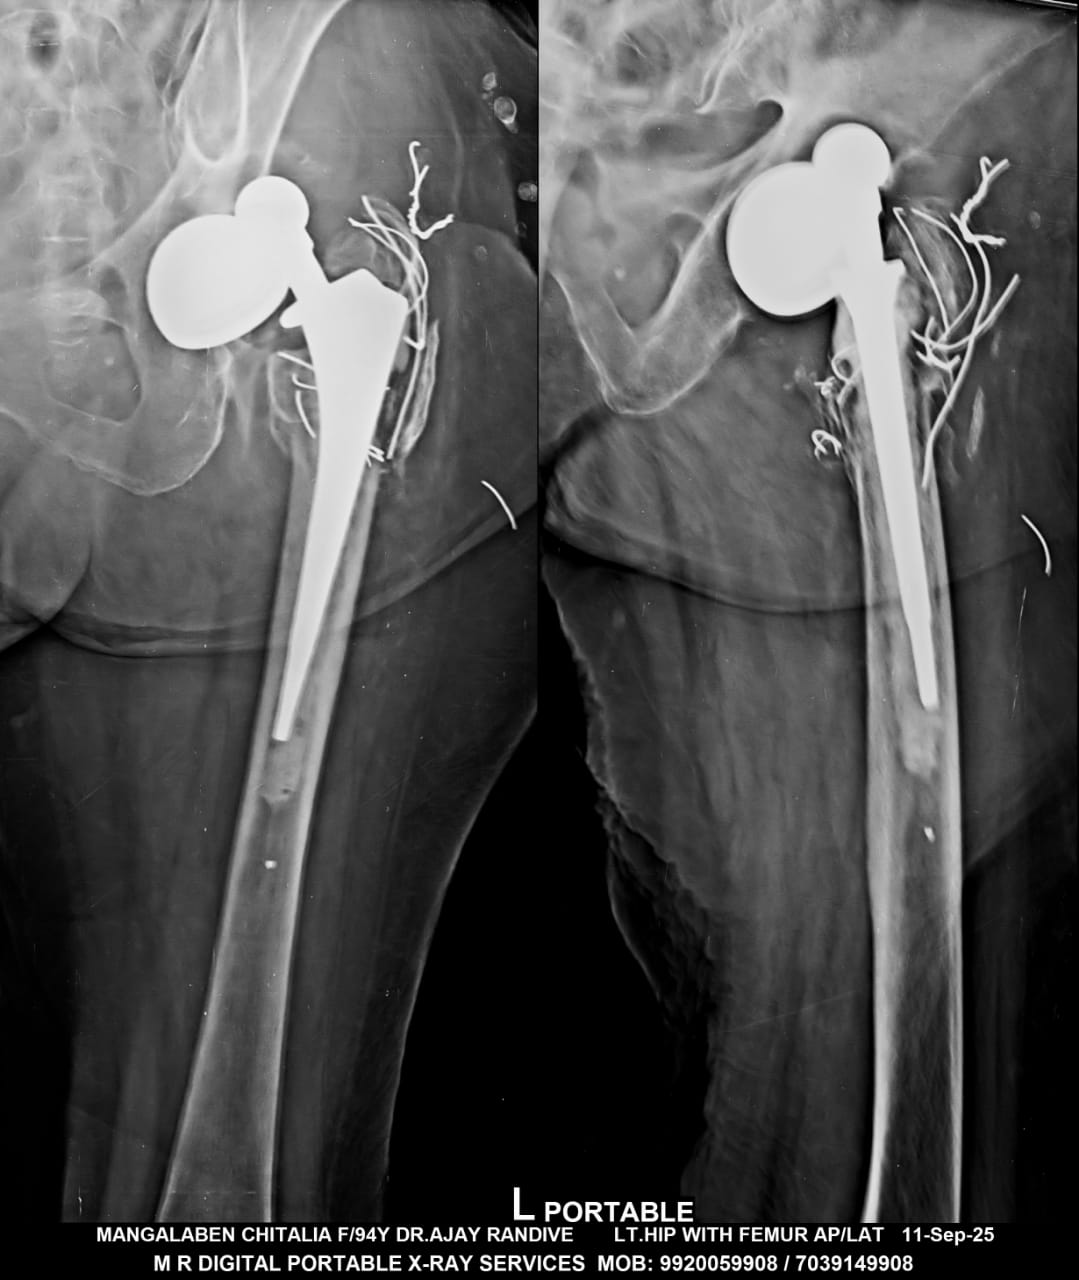

Dr Ajay Randive : IS MS Ortho (Mumbai) MRCSI ( UK) Consultant knee, Hip ,& Spine Surgeon, Dr Ajay Randhive is a eminent Knee, Hip , & Spine Surgeon practicing in to areas Andheri East,Santacruz East. Dr Ajay Randive did his MS Ortho residency from LTMMC, Sion Hospital Mumbai. He did overseas training in UK from 2003 till 2008. He is trained in total Knee Replacement, Hip Replacement, Revision Hip Replacement And Revision Knee Replacement Surgeries. He has worked at The Royal London Hospital. IN London where he worked a clinical fellow in joint Replacement unit. He has carried out more than 5000 Knee Replacement surgeries, 2500 Hip Replacement Surgeries, More Than 500 Revison Knee And Hip Replacement Surgeries 600 Spine surgeries & more than 1500 arthroscopic surgeries (Knee & Shoulder).